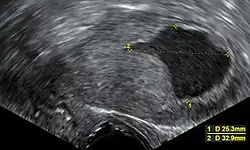

| Location | Mean (mm) | Range (mm) |

| Anterior wall | 23 | 17 - 25 |

| Posterior wall | 21 | 15 - 25 |

| Fundus | 20 | 15 - 22 |

| Isthmus | 10 | 8 - 22 |